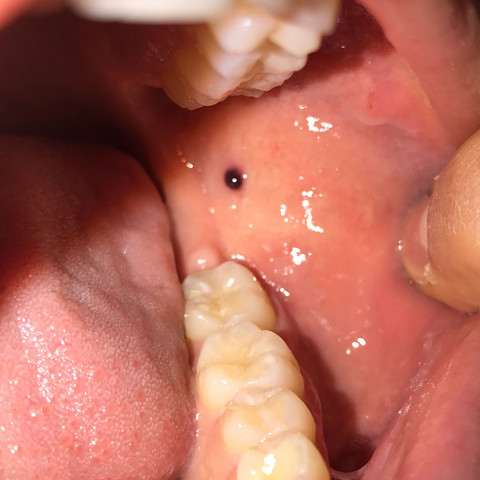

Schwarzer Punkt Im Mundraum Bekommen Was Ist Das Siehe Bild Gesundheit Und Medizin Gesundheit Medizin

Was Ist Das Fur Ein Schwarzer Punkt Im Mundraum Arzt Mund